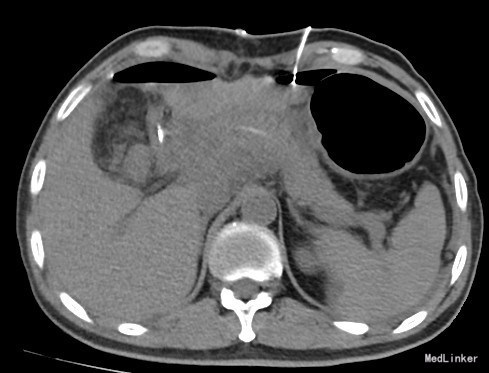

患者男,45岁,主因“上腹胀痛9月余,体检发现胃占位5月”以“1.胃恶性肿瘤十二指肠浸润 2.恶性肿瘤术前化疗后 3.腰椎管狭窄 4.右下肢静脉曲张术后 ”收入院。患者于9月前无明显诱因出现上腹部饱胀感,后间断出现胀痛,疼痛不向其他部位放射,无特殊缓解方式。进食无不适,食欲无改变。无烧心返酸、恶心呕吐。在当地医院口服药物治疗,自觉症状好转。5月前患者出现呕吐,为胃内容物,并出现黑便。就诊垂杨柳医院,行胃镜检查,结果示:胃窦后壁可见巨大溃疡占位,约5*4cm,延续至幽门,十二指肠球部后壁可见巨大溃疡,约1.0*1.8cm。病理活检示胃窦低分化腺癌。考虑直接手术可能性小,后于我院先行四次化疗,此次为进一步手术治疗入我科。

胃恶性肿瘤十二指肠浸润 胰十二指肠切除术